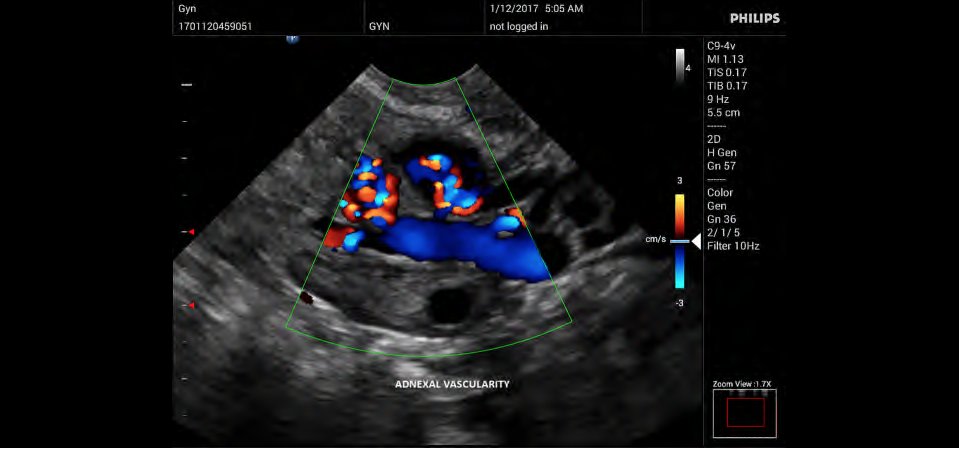

• Конвексный УЗИ датчик Philips C9-4v

• Цветное допплеровское картирование

• Направленный энергетический допплеровский режим: Дополнительно к возможностям визуализации сосудов в стандартном энергетическом режиме добавляется информация о направлении. Этот режим полезен для визуализации мелких сосудов в качестве замены цветного допплеровского картирования.